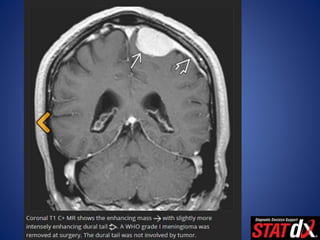

• T1WI C+

– > 95% enhance homogeneously, intensely

– Dural tail (35-80% of cases) nonspecific

• Other neoplasms (schwannoma, adenoma, metastases), nonneoplastic

dural-based masses

– En plaque: Sessile thickened enhancing dura

• T1WI C+ –> 95% enhance homogeneously, intensely – Dural tail (35-80% of cases) nonspecific • Other neoplasms (schwannoma, adenoma, metastases), nonneoplastic dural-based masses – En plaque: Sessile thickened enhancing dura • MRV – Evaluate sinus involvement • MRS – Elevated levels of alanine at short TE • Triplet-like spectral pattern at 1.3-1.5 ppm (overlapping of Ala, Lac) • Elevated Glx alfa/glutathione